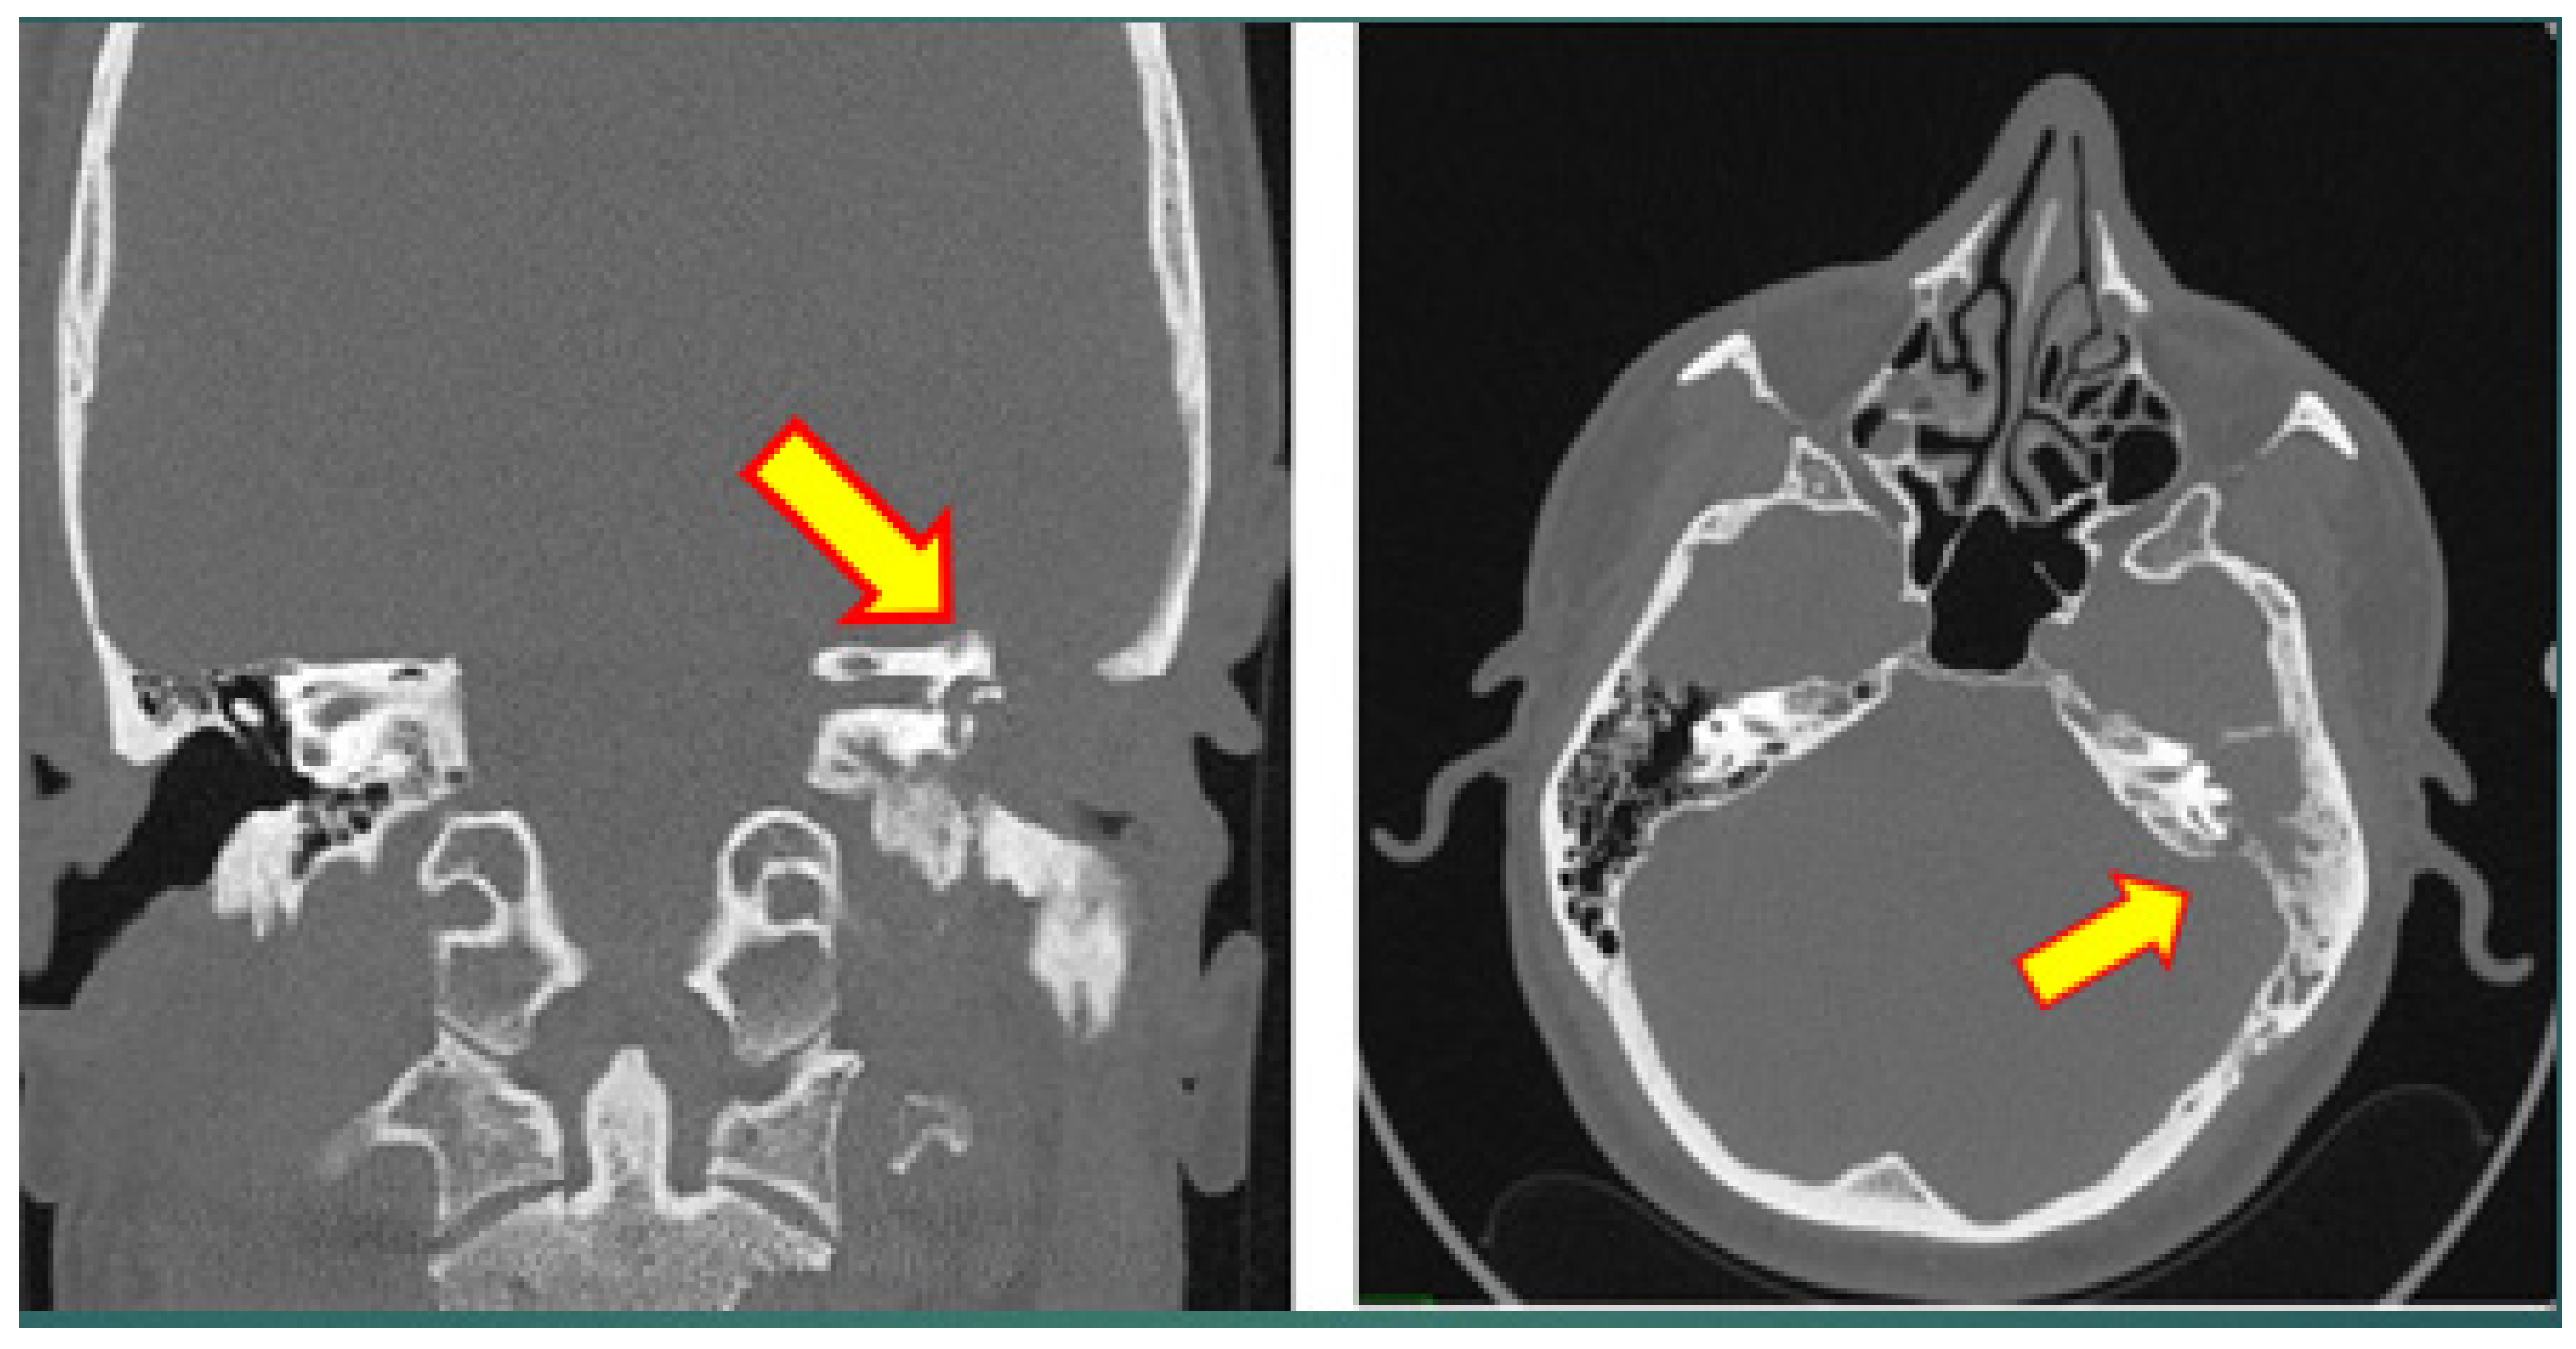

3.2. Case 2

| 19 | 2021 | Israel | Present study | 44 | m | otitis media | 1 | - | fibrous tissue, dense lymphoplasmacytic inflammation, storiform fibrosis | IgG4 25 per HPF; IgG4:IgG < 20% | Data not available |